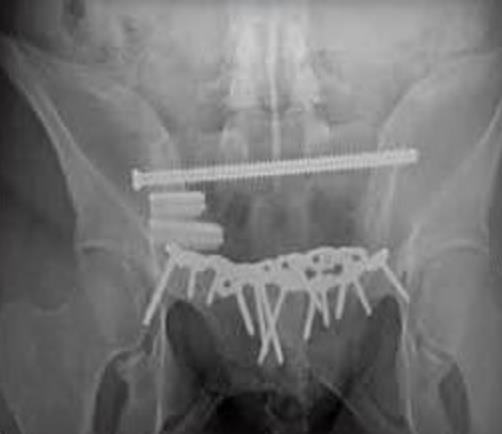

• iFuse-3D is a minimally invasive implant system intended to stabilize and fuse the sacroiliac joint by delivering triangular, porous, fenestrated titanium implants across the joint via a percutaneous approach.

• Triangular-shaped implant profile minimizes rotation, with more than 6× the rotational resistance of a screw, and stabilizes the joint while the porous surface supports long-term fusion.

• Minimally invasive lateral or oblique trajectory through a small incision with percutaneous instrumentation to place triangular implants across the SI joint.

• Triangular implants differ from cylindrical screws by engaging osseous walls with an interference fit that improves rotational stability for SI fixation.

• The geometry demonstrates more than sixfold rotational resistance compared with a screw.